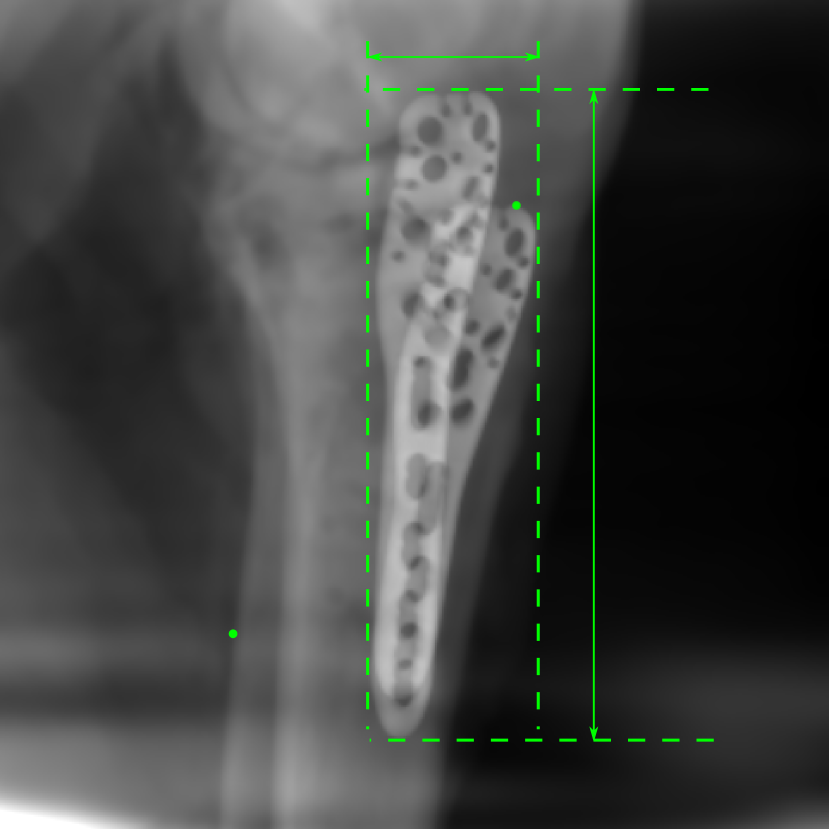

Figure 14: The results for the real cadaver leg data. The green dots mark the positions of landmarks in the corresponding reference images. In the first column, the arrows indicate the bone cavity/fracture structures. In the second column, the solid lines mark the widths and heights of the metals. The green ones are measured from the DRR reference, while the red ones are measured in the corresponding perspective projection image. In the last column, the lines mark the centerlines of the metal screws, where the green lines are those from the reference image. The lengths of the lines in mm are displayed in their corresponding subcaptions. Intensity window: [0, 4]. Please zoom in for better visualization.

The complementary view setting for learning perspective deformation is also evaluated on real CBCT projection data. In this evaluation, real CBCT projection data from a dataset of knees with metal implants is used for testing, while DRRs created from volumetric CT datasets with inserted metals is used for training. Three exemplary DRR perspective projection images for training are displayed in Fig. 13, in which synthetic metal implants are inserted [34]. The appearance, e.g., image contrast and metal image resolution, of such DRR training images is different from that of real projection images in Fig. 14. In Fig. 14, the results for three knees, with and without metal implants, are displayed. The first and second rows are the 0superscript00^{\circ} and 180superscript180180^{\circ} perspective projections, respectively, rebinned to the virtual detector with geometric calibration based on their respective principal points and projections of the world origin. The third row displays their difference images, where the magnitude of deviation increases from the center towards the outside like it does in DRRs with an ideal scan trajectory (e.g., Fig. 6(e)), although real projection data suffer from various physical effects like beam hardening and Poisson noise. The fourth row displays the RGB stacks of 0superscript00^{\circ} and 180superscript180180^{\circ} perspective projection images. The magenta and green regions indicate structures with considerable perspective deformation, for example, the knee patella in Fig. 5.4, the top parts of the two metals in Fig. 5.4, and the bottom two screws in Fig. 5.4. The fifth row displays reference images, which are orthogonal projections of iterative reconstruction volumes from measured CBCT projection data. In the reference images, a total of five landmarks are selected, with the positions being marked by the green dots: In Fig. 5.4, two positions at the edges of the knee patella are marked; In Fig. 14(e) and Fig. 14(f), one position at the left edge of the fibula is marked for each image. In addition, a rectangular frame for the two metals is marked by the green dashed lines, while its width and height are indicated by the green solid lines, which are 29.71 mm and 111.99 mm, respectively. In Fig. 14(f), the centerlines of the bottom two screws are sketched by the green lines, which have the lengths of 17.14 mm (middle screw) and 19.38 mm (bottom screw). The corresponding rectangular frame for the two metals and the screw centerlines in the perspective projection images are marked as well, but in red color. In Fig. 14(a), the width and height of the metals are 32.56 mm and 109.85 mm, which have deviations of 2.84 mm and -1.95 mm to the reference ones, respectively. In Fig. 14(b), the centerline lengths are 18.91 mm and 19.54 mm, which have deviations of 1.77 mm and 0.16 mm, respectively. Although the bottom screw has little length deviation to the reference, the orientations of both screws are obviously deviated. The sixth row shows the results of Pix2pixGAN using 0superscript00^{\circ} and 180superscript180180^{\circ} polar inputs. For all of the landmarks, the green reference dots are all located accurately in the Pix2pixGAN images. The rectangular reference frame also accurately covers the metals in Fig. 14(g). In Fig. 14(h), although the two red centerlines do not exactly overlap with the green one, they are very close in lengths and orientations. Please zoom in for better visualization.